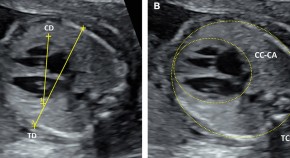

Comparing three cardiothoracic ratio measurement techniques and creating multivariable scoring system to predict Bart’s hydrops fetalis at 17–22 weeks’ gestation

- Sanitra Anuwutnavin

- Patsawee Rangseechamrat

- Sommai Viboonchard